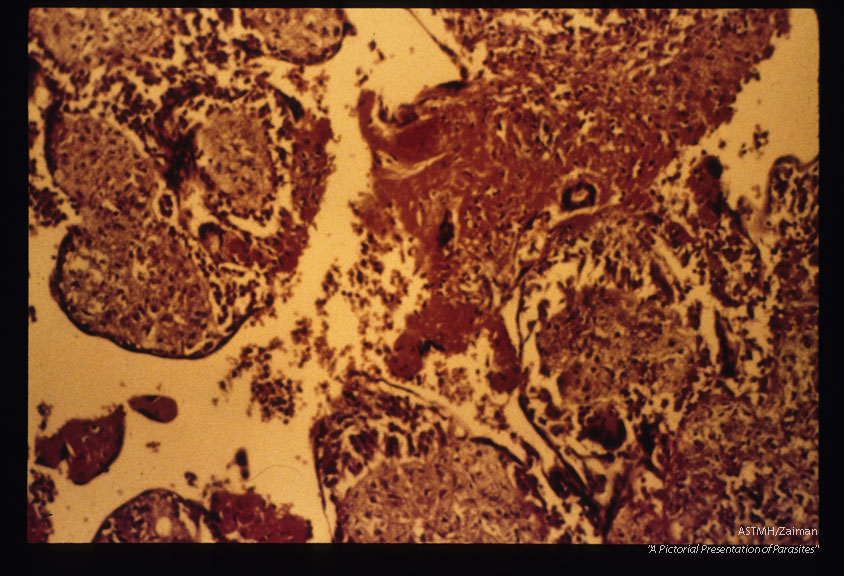

Granulomatous reaction in the placenta secondary to infection.

Trypanosoma cruzi

Description: Granulomatous reaction in the placenta secondary to infection.